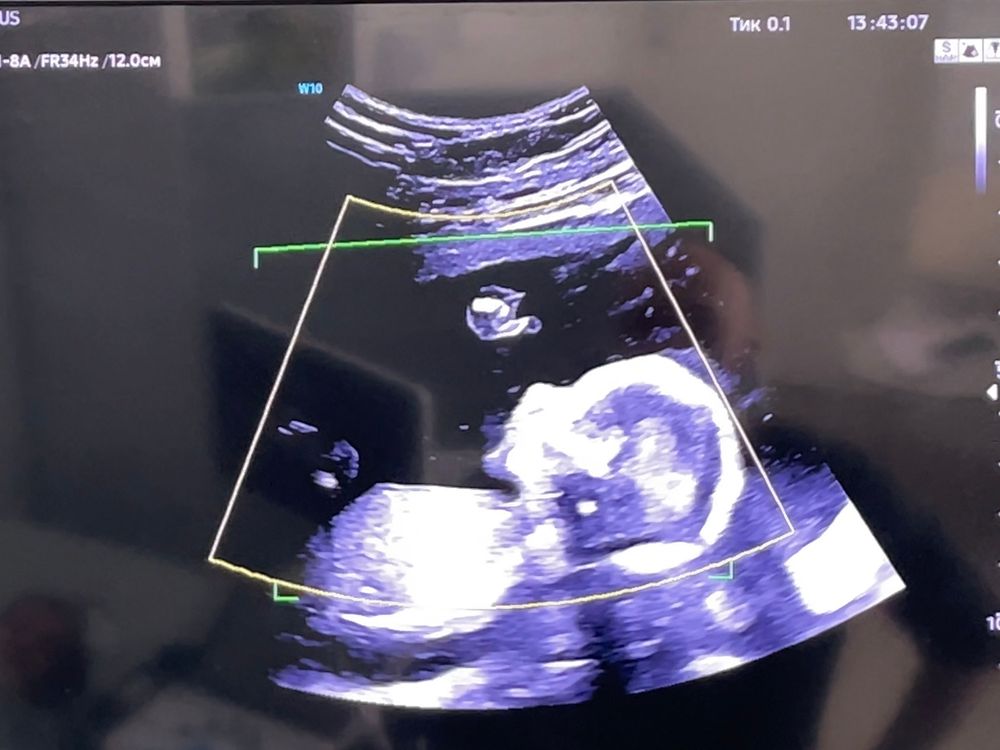

❤ Девочка!))) Я очень рада))❤

Сегодня был 2 скрининг: урааааа, девочка!)))) Показывает 👍🏼 на фото))